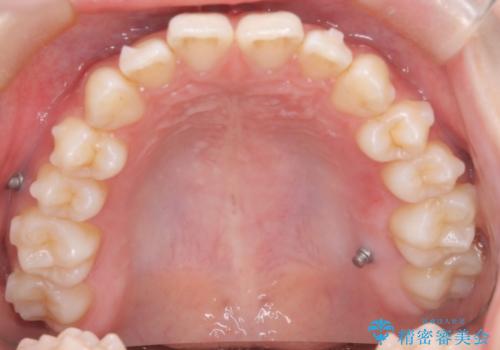

初診時の歯並びの状態としては、上下前歯が噛んでいない開口という状態であり、前歯を中心に上下とも歯の間に隙間がある状態でした。

抜歯は行わずマウスピース治療による主訴の改善を計画しました。